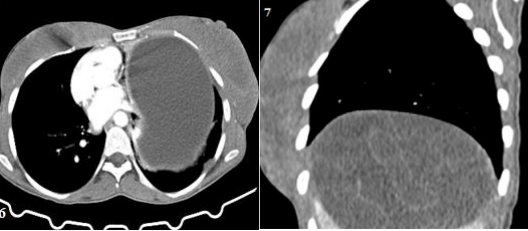

The patient's ECG showed normal sinus rhythm, and her myocardial-specific enzyme levels were within the normal range. A cystic lesion was found to be causing pressure on the left ventricle and atrium on the lateral wall of the pericardium, as revealed by CXR and CT scans. Abdominal ultrasonography and contrast-enhanced CT scans confirmed the presence of a large hydatid cyst lesion with septation in the liver (Figure 6,7,8).

Figure 6: shows a CT scan with a substantial cystic lesion of the left lung, which compressed the heart and mediastinum, carina, and liver cyst.

Figure 7: shows a coronal CT scan of the liver with huge cystic, septation, and laminated membrane.

Figure 8: shows a CT scan of the liver with huge cysts, septation, and a laminated membrane in another view.